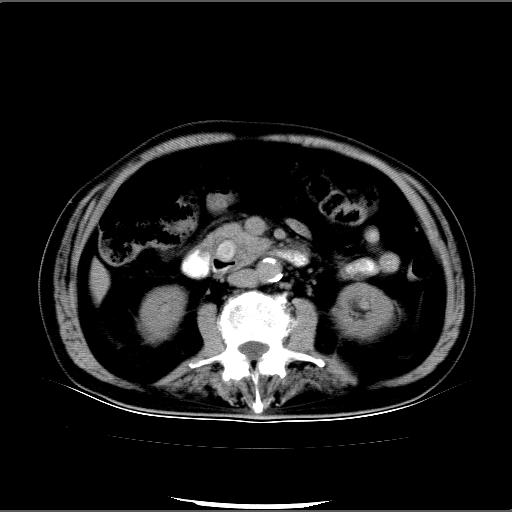

患者男82岁,黄染,发热10天,无腹痛。

1胆总管下端结石伴肝内外胆管扩张;2胆囊颈部结石伴胆囊积液

胆囊多发结石,胆囊积液;胆总管中下段结石,中上段扩张。

胆总管下段结石伴胆道系统扩张;胆囊炎伴胆囊结石.

1、胆总管壶腹部结石并胆总管、胆囊及肝内胆管扩张。2、胆囊多发结石。3、两下胸膜局限性增厚。4、胃体部大弯侧胃壁稍厚,建议:多量饮水后增强ct扫描除外占位性病变。

此病例有结果了:患者术后为:胆总管下段结石伴胆道系统扩张;胆囊炎伴胆囊结石。

各位战友分析的都很正确,是一个典型的病例。